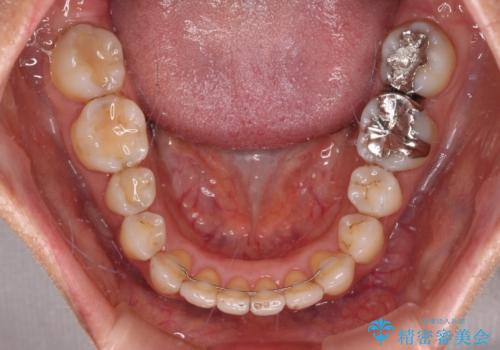

インビザライン・ライトは提供されるマウスピースの数に制限があり、通常のタイプよりもマウスピース提供期間が短くなっている一方、安価に治療を行うことができるプランです。

治療のゴールも変更できないため、軽微な歯列不正や、後戻り改善などに適しています。